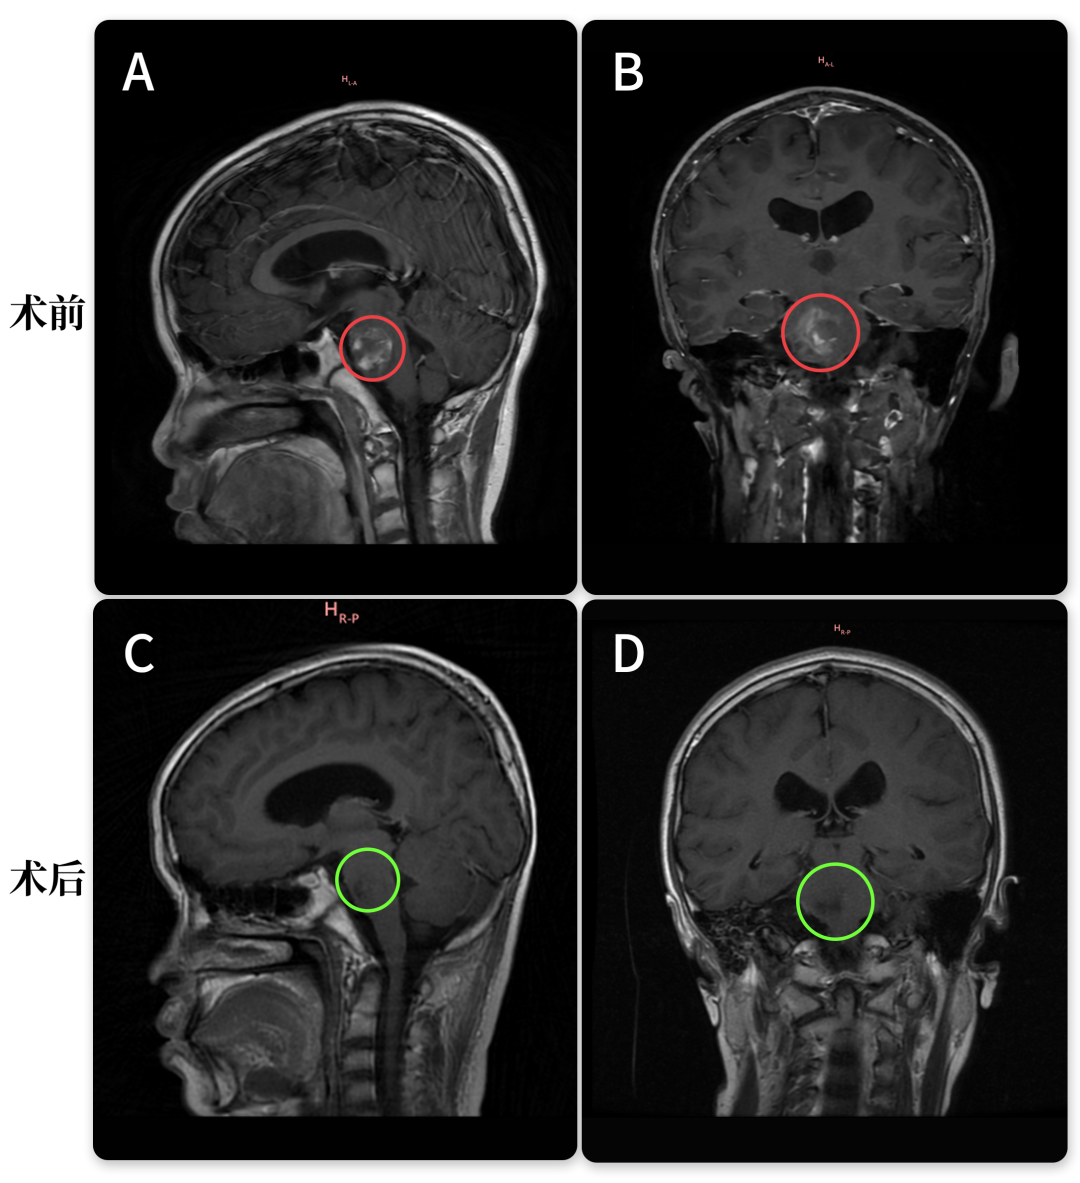

然而,3个月后的复查却险些将小雨一家拽回到曾经的噩梦中。复查报告上显示:脑干存在异常信号,考虑海绵状血管瘤;此外,核磁还发现了一个位于右侧天幕下的蛛网膜囊肿。寝食难安的父母赶紧联系了巴教授,没想到,巴教授却大笑说:别担心,这是好消息!

看完小雨的新影像资料,巴教授远程评估表示:“好消息!男孩临床状况很好,这也与核磁共振检查结果相对应。”又3个月后,小雨妈妈得知巴教授即将来华,于是她带着孩子来到了苏州,除了想再次当面好好感谢教授之外,也想要让教授亲自看看孩子的情况。

原来,报告上的“异常信号”并非当初残余的肿瘤,而是含铁血黄素的残留,这对于小雨当初如此巨大出血性的脑干病变来说是正常的,它并不是活跃性的海绵状血管瘤。

尽管不久后小雨一家成功找到巴教授手术,并全切了海绵状血管瘤,但之前的2次脑干出血也为此次“乌龙”埋下了伏笔。

原来,由于脑干海绵状血管瘤极易反复、微量出血,当脑组织存在慢性出血或血管损伤时,其残留的代谢产物就会导致含铁血黄素沉积。当然这并非一种需要治疗的疾病,正如巴教授所说,这在小雨这样如此巨大的海绵状血管瘤全切术后是正常现象。